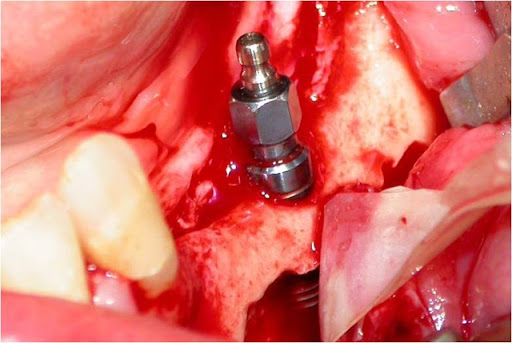

Figs. 8, 9 e 10 - Os implantes já perfeitamente fixados, com a suave deposição do plexo alveolar inferior na sua loja cirúrgica.

Uma vez localizado o canal mandibular sua parede é cuidadosamente retirada, liberando-se progressivamente o feixe neurovascular. Eventualmente, por uma outra técnica há necessidade de se realizar a transposição do nervo incisivo para se obter um afastamento satisfatório do NAI. Após o afastamento do feixe, realiza-se a fixação dos implantes, seguindo o protocolo correspondente, utilizando-se da cortical basal ou não, para obter uma melhor estabilidade inicial (24, 30) (Figs. 8, 9 e 10). Na seqüência o NAI é acomodado passivamente na loja óssea quando apenas lateralizado (12, 29).